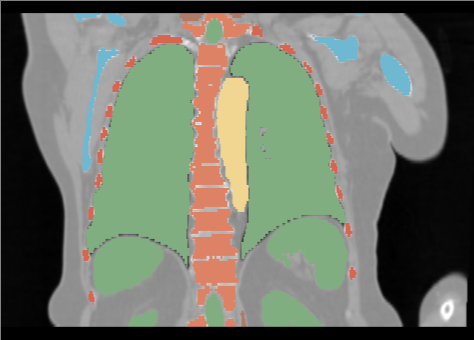

We developed a tailored version for our dataset: CT volumes were segmented using the standard TotalSegmentator, and the resulting labels were used to train a new nnU-Net segmentation model adapted to our resolution ( mm). Labels were merged into a compact mapping:

CLASS_MAPPING = {

"organs": 1, "cardiac": 2,

"muscles": 3, "bones": 4,

"ribs": 5, "vertebrae": 6

}

We call this network TS_Compact7_3x1x1 and use it for AFP feature extraction. This network is designed to be easily trainable by reducing the number of classes from over 100 to a manageable set, is compatible with all three datasets (HN, AB, TH), and is adapted to our pixel spacing so that it can provide meaningful features for the synthesis process using the AFP loss.

Figure 1 illustrates a comparison of axial slices between the original CT from the TH dataset, segmentation by TotalSegmentator, and the corresponding segmentation produced by TS_Compact7_3x1x1..